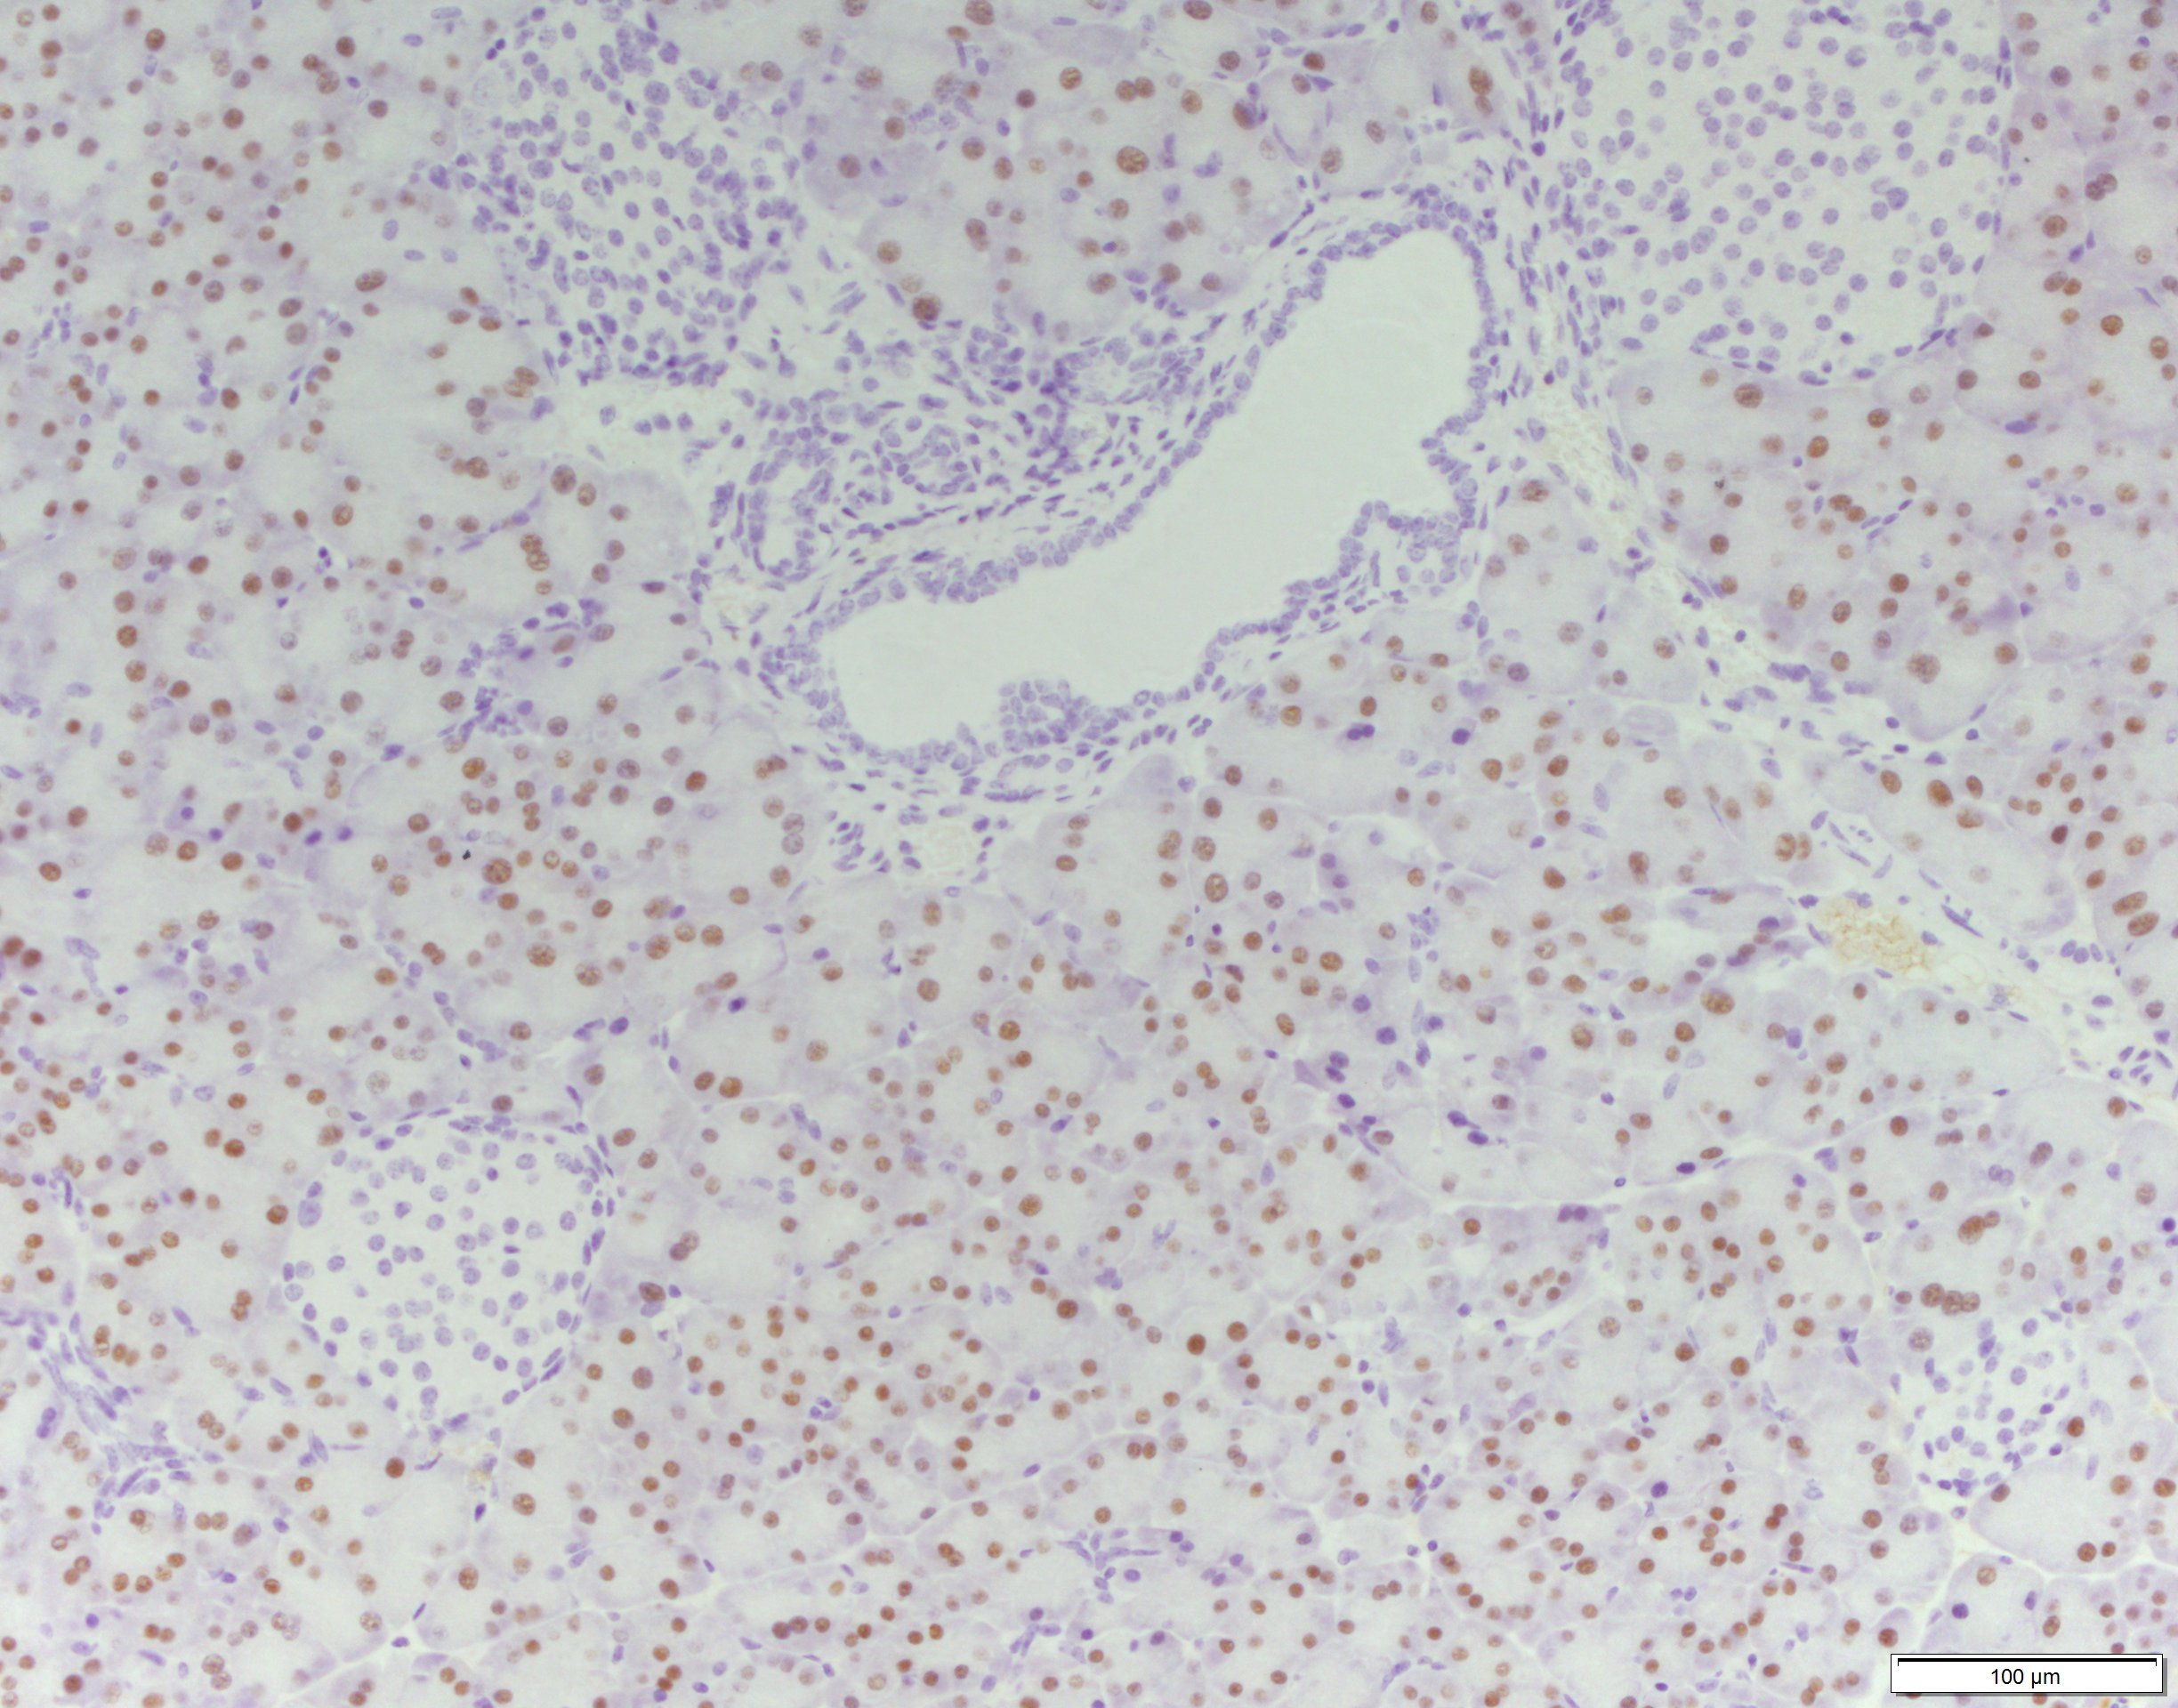

Paraffin-embedded sections

Antigen retrieval: Citrate pH=6

Mouse pancreas